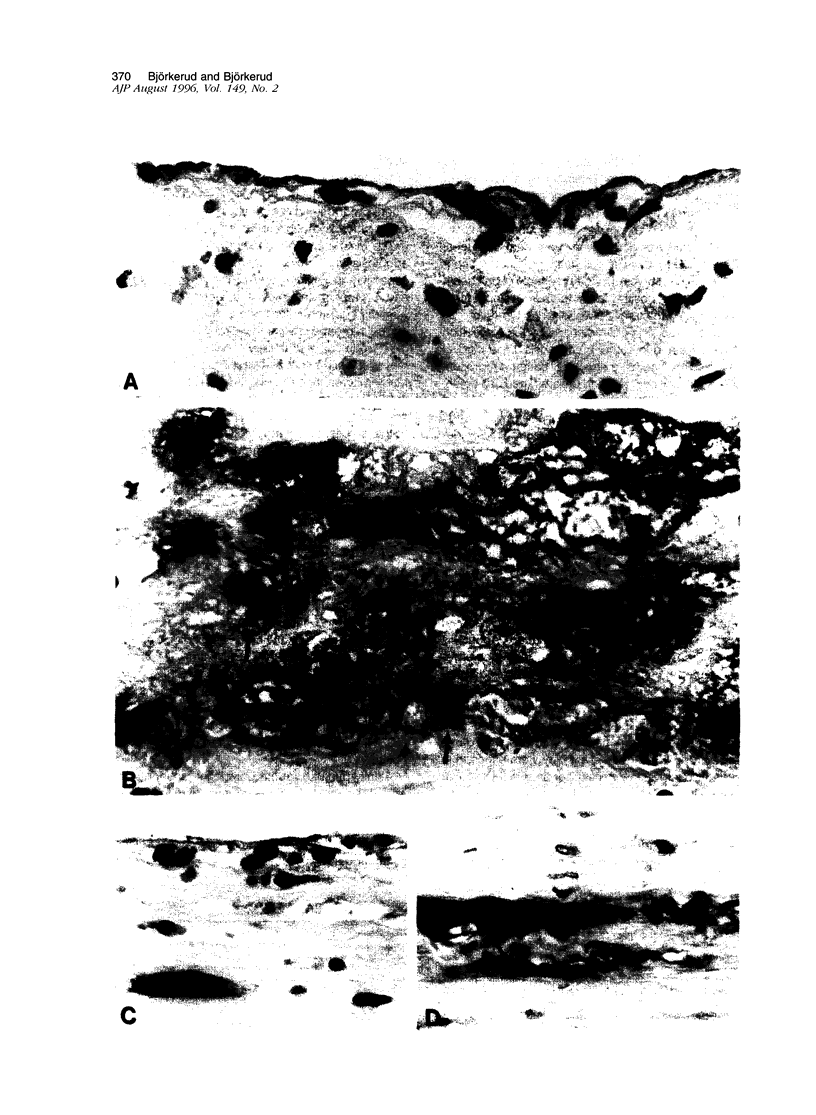

Death of intimal tissue may lead to plaque rupture with thrombosis, which is the basis of the most severe clinical consequences of atherosclerosis. Little is known about the mechanisms that promote intimal cell death or its nature. This work was undertaken to elucidate the extent to which, the cell types in which, and where programmed cell death, apoptosis, might occur in atherosclerotic lesions. The material was fibrous or fibro-fatty non-ulcerated lesions from the human thoracic aorta and coronary arteries. Apoptosis was indicated by the in situ labeling of internucleosomally degraded DNA with the TUNEL technique, which has a preference for apoptosis as compared with cell necrosis and was combined with the immunohistochemical typing of cells. Apoptosis was corroborated by morphological criteria on the light and electron microscope levels and by the presence of an apoptosis-specific protein. It was common in the lesions and virtually absent in non-atherosclerotic regions. It occurred in smooth muscle cells subendothelially, in places of the fibrous cap, and in the underlying media, which may destabilize the plaque and promote rupture. Inflammatory cells, ie, macrophages and T cells, appeared abundantly subendothelially, in the fibrous cap, and in the shoulder regions, and apoptosis was common, maybe reflecting a means for quenching of the inflammatory reaction. Many macrophages contained abundant apoptotic material indicative of phagocytosis of apoptotic cells, but the occurrence of apoptosis, even in some of these cells, and of apoptotic material extracellularly and the very high numbers of apoptotic cells that were encountered may indicate insufficient mechanisms for the removal of apoptotic cells in the atherosclerotic lesion. It is not possible to decide as yet whether this is due to overloading with cellular material by inflammation and cell multiplication, to an increased frequency of apoptosis, to a reduction of the removal/degradation of apoptotic material by macrophages, or a combination of these factors.